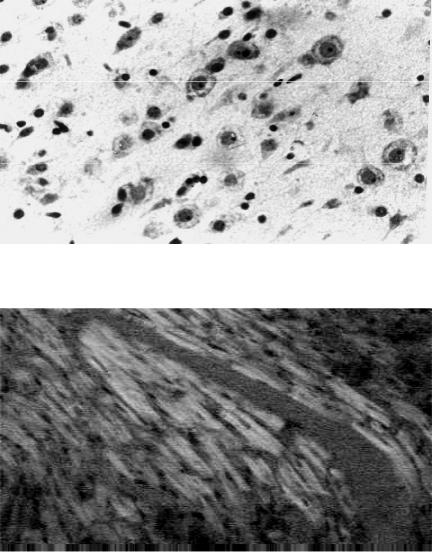

В головном мозге снижение кровотока при шоке приводит к появлению ишемически измененных невроцитов ишемической энцефалопатии (рис. 39).

Рис. 39. Микропрепарат

головного мозга при ишемической энцефало- патии: очаговый

лизис нейронов в слое пирамидных клеток серо- го вещества коры голов- ного мозга (окраска гема- токсилином и эозином, × 500), рисунок Н.Д.

Клочкова